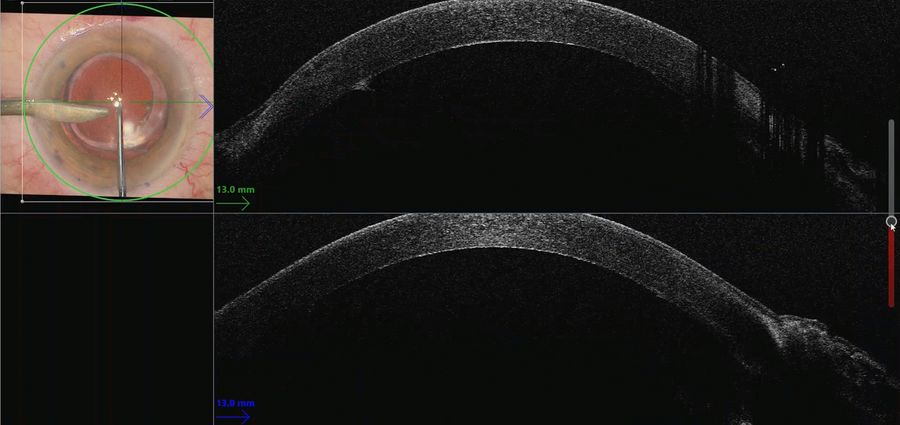

The use of intraoperative OCT can help overcome the challenges of endothelial keratoplasty through real-time information supporting decision-making. Endothelial keratoplasty is a surgical procedure to replace a damaged endothelium with healthy donor tissue, which includes both DSEK and DMEK techniques.

- Understand the role of intraoperative OCT, in particular for the successful orientation and positioning of the donor tissue in DSEK, DALK and DMEK procedures.

When performing the strip, the intraoperative OCT provided live confirmation of where DM was present. This is particularly helpful when there is a poor view e.g. in this case of ocular trauma. The OCT showed the separation of Descemet’s membrane very clearly.